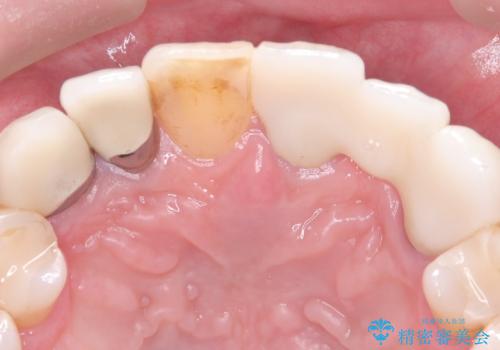

左上1番目~3番目にかけてブリッジの仮歯が入った状態で来院された患者さんで、左上3に縁下カリエスを認め抜歯してインプラントか牽引(エクストリュージョン)を行うか、歯肉根尖側移動術を行うか選択いただき牽引の後補綴処置を行うこととしました。

左上3の牽引を1か月半ほど行った後、補綴治療を行っています。

両支台歯とも根尖病巣は認められなかったため、ファイバ-コアからのやり替えとしました。